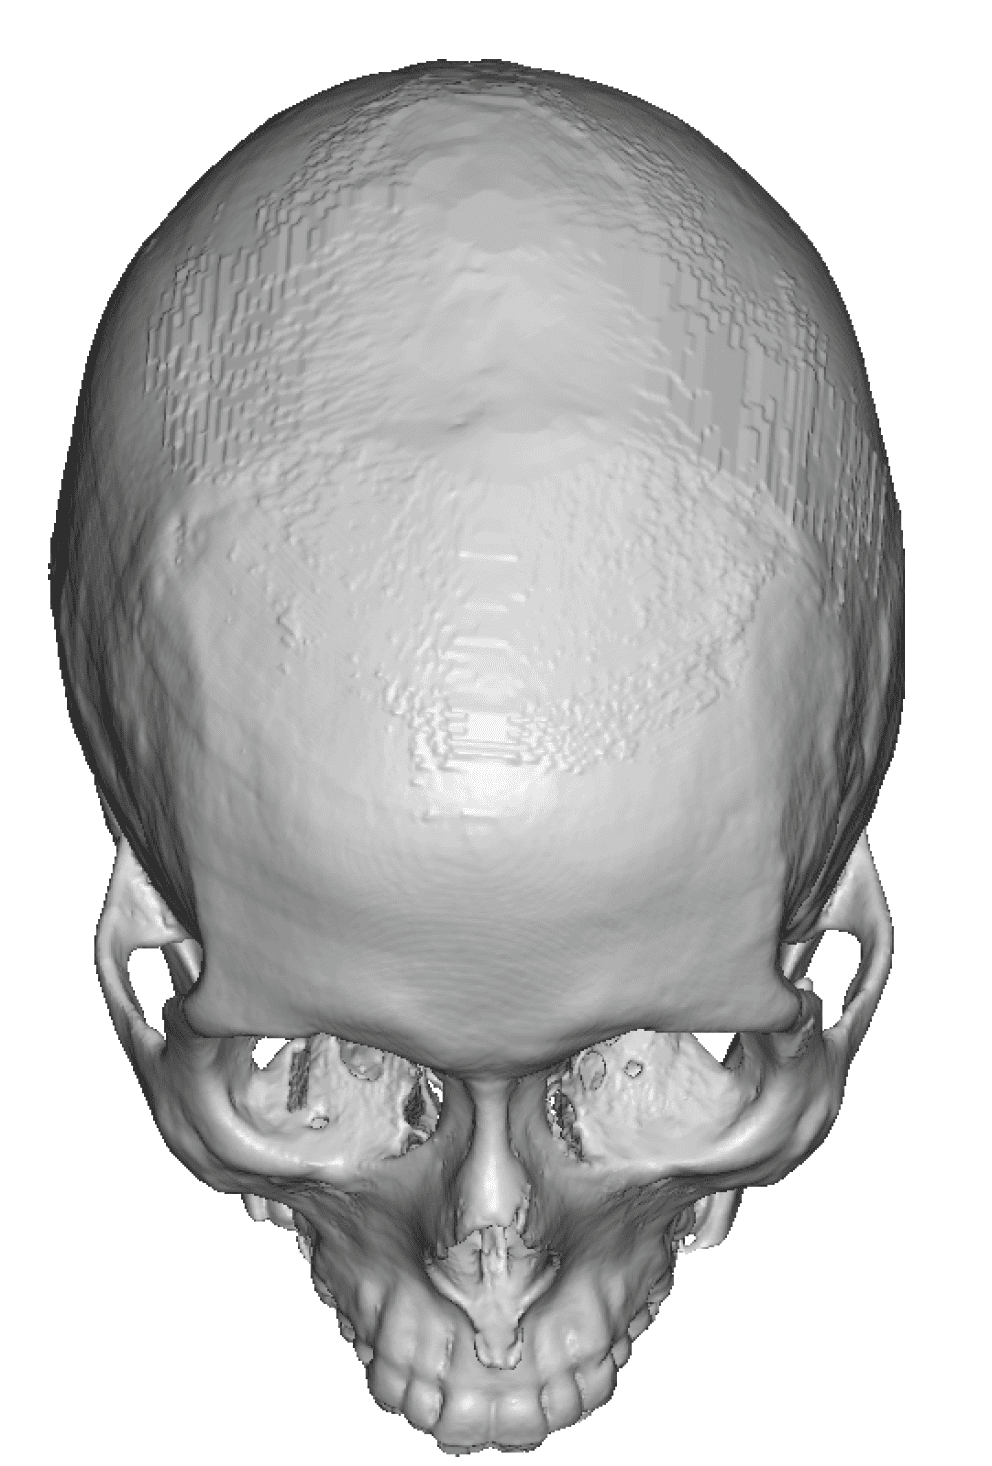

Patient 49

Desire for further skull augmentation after a primary skull implant.

Five years after an initial custom skull implant placement a new custom skull implant that increased the volume by 35% was placed.

Desire for further skull augmentation after a primary skull implant.

Five years after an initial custom skull implant placement a new custom skull implant that increased the volume by 35% was placed.